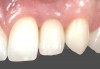

Fig 1. Case 1: A horizontal releasing incision across the edentate ridge at the site of tooth No. 8. It terminates 1 mm from the adjacent teeth.

Figure 1